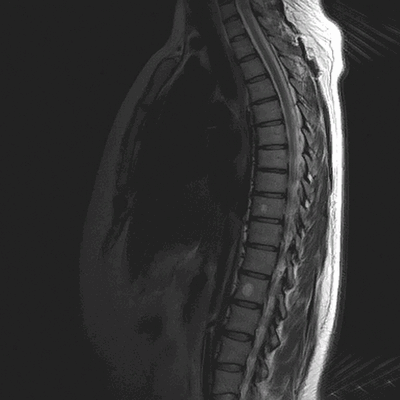

МРТ грудного отдела позвоночника (сагиттальная проекция, Т1 ВИ)

Магнитно-резонансные томограммы отображают внутренние структуры зоны интереса в трех плоскостях. Каждый снимок представляет собой один срез, на распечатанном фото МРТ их несколько.

В норме позвонки гладкие, повреждения отсутствуют. Фиброзно-хрящевые диски, выполняющие роль амортизаторов, не выпячиваются, имеют стандартную высоту, без признаков дегенерации. Спинной мозг выглядит на фото как белый шнур без видимых перекосов и других изменений.